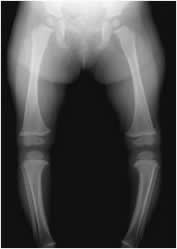

El niño desde el nacimiento hasta los 24 y 30 meses, puede presentar un genu varo fisiológico. (Fig 68). Este debe ser bilateral y con una distancia menor de 6 cm, entre los cóndilos femorales. El ángulo del eje femorotibial no debe ser mayor de 28º y no requiere de tratamiento. Si el genu varo persiste después de los 36 meses, se debe diferenciar del raquitismo, la enfermedad de Blount (Retardo en el crecimiento posteromedial de la tibia, la cual es mas corta), malformación congénita, infección, trauma, osteoartrosis, etc. (1). (Fig 69 y 70).

Fig 68. Genu varo.

Rx AP: Lactante con genu varo bilateral, durante su desarrollo normal.